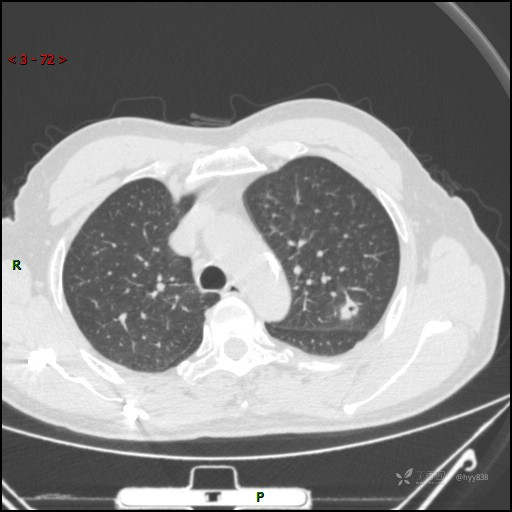

又遇恼人的肺结节,囊腔 VS 空洞 VS 空泡,欢迎讨论---结果公布~

患者年龄:61岁

主诉:发现左肺结节半月

简要病史:患者半月前因双眼翼状胬肉于我院眼科就诊行手术治疗,完善胸部CT发现左肺结节,未行特殊处理,偶有刺激性干咳,每于受凉后及饮冷水后发作,休息后可自行缓解,无发热、恶心呕吐、胸痛咯血,现为求进一步诊治,于我院就诊,门诊以“左肺结节”收入我科。 起病以来,患者食欲尚可,大小便正常,睡眠、精神可,体力、体重无明显变化。

临床诊断:肺结节

胸部CT平扫